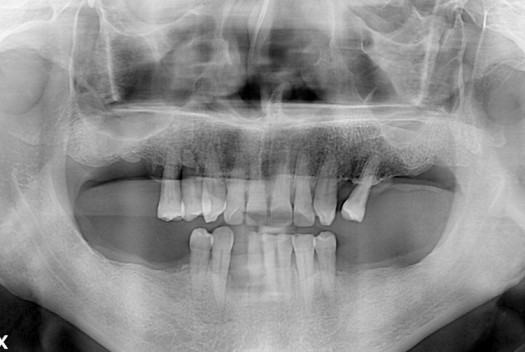

치료전 : 2018-03-31

PX20180331_100013_0248_00000000.jpg

세종치과는 많은 환자와 다양한 케이스를 바탕으로 항상 편안한 임플란트 수술을 제공하고자 노력하고,

오래동안 튼튼히 쓸 수 있는 임플란트 수술을 가장 큰 목표로 삼고 있습니다.